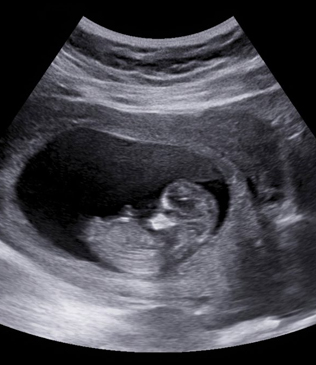

Obstetric ultrasound is a safe and non-invasive imaging technique used during pregnancy to monitor the health and development of the baby inside the uterus. It uses high-frequency sound waves to create images of the fetus, placenta, and surrounding structures, allowing doctors to assess the progress of pregnancy and detect any potential concerns.

This type of ultrasound plays a crucial role in prenatal care by helping healthcare providers track fetal growth, confirm the baby’s position, evaluate the placenta, and monitor amniotic fluid levels. Obstetric ultrasound examinations are routinely performed at different stages of pregnancy to ensure both the mother and baby are healthy and progressing normally.